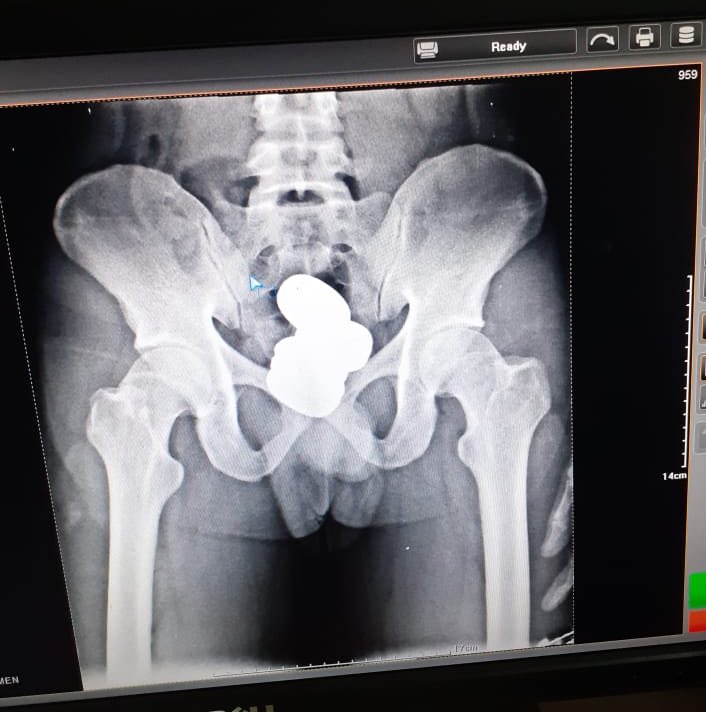

根据英国《独立报》报道,谢里夫被海关人员带进体检室照X光,在他的直肠内发现,居然藏有4颗装有膏状黄金的胶囊。

对此,印度中央工业安全部队(CISF)表示,谢里夫体内的黄金重约909.7克,要价约420万卢比(约23.6万令吉)。